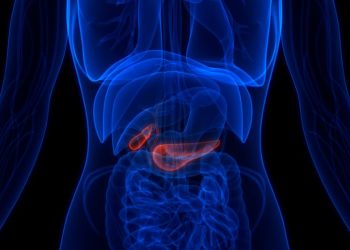

The pancreas produces enzymes that help the body digest food. When cancer develops in the pancreas, it can affect the...